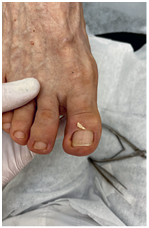

Иллюстрация к книге — Подология понятно. Важен каждый шаг. Справочник по проблемам подологии для клиентов и мастеров эстетики [i_269.jpg]

Иллюстрация к книге — Подология понятно. Важен каждый шаг. Справочник по проблемам подологии для клиентов и мастеров эстетики [i_270.jpg]

Иллюстрация к книге — Подология понятно. Важен каждый шаг. Справочник по проблемам подологии для клиентов и мастеров эстетики [i_271.jpg]

Иллюстрация к книге — Подология понятно. Важен каждый шаг. Справочник по проблемам подологии для клиентов и мастеров эстетики [i_272.jpg]

Результат работы за 5 месяцев: подолог использовал крючковые коррекционные системы, а хирург сделал пластику внутреннего бокового валика (из-за хронических воспалений боковой валик стал гипертрофированным и давил на ноготь, от чего клиент испытывал постоянный дискомфорт)